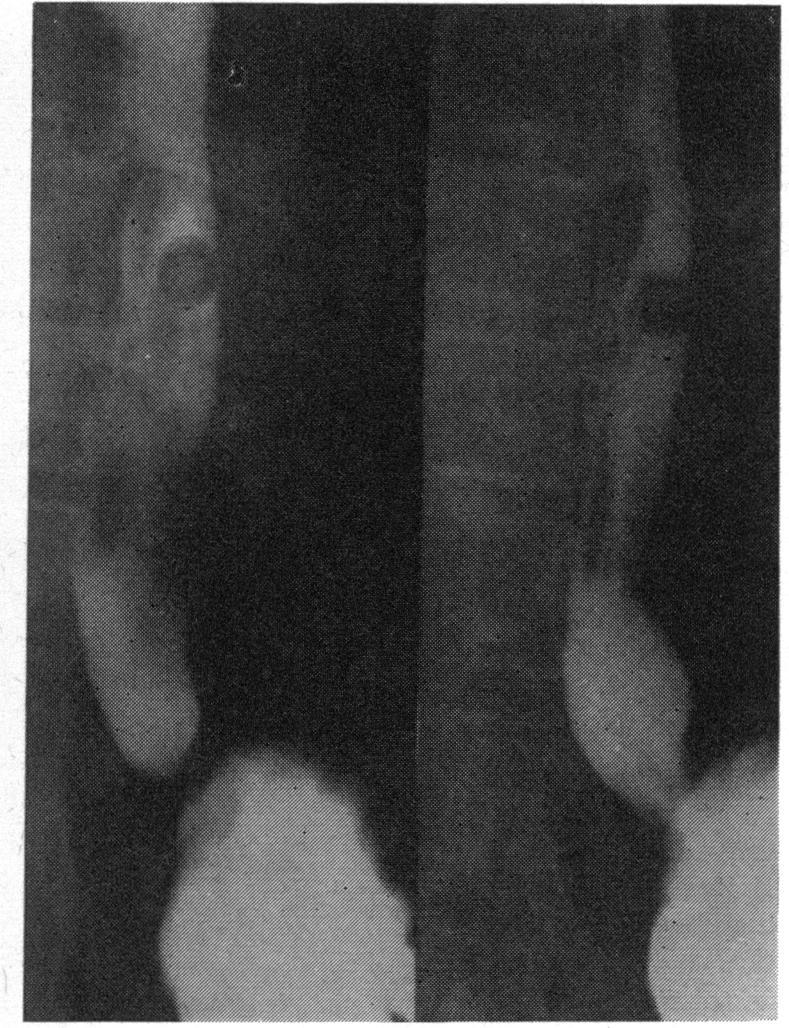

A case is described of oesophageal ulceration and hold up following oral potassium therapy. The patient had recently undergone mitral valve replacement.

描述了一例口服钾治疗后出现食管溃疡和梗阻的病例。该患者最近接受了二尖瓣置换术。